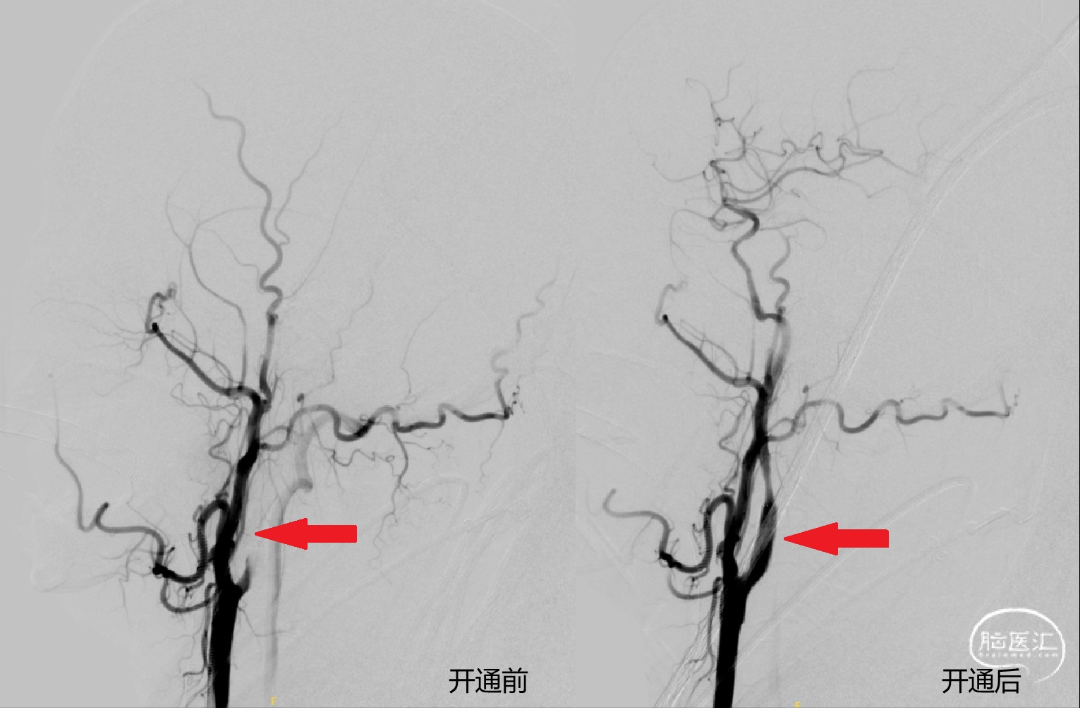

近期,中国医科大学附属第一医院卒中中心李志清主任(点击进入个人主页)及其团队采用球囊接力技术成功救治颈动脉全程闭塞致急性脑梗死患者。现患者恢复良好,已顺利出院。

点击查看原文:《医路前行|卒中中心采用球囊接力技术成功救治颈动脉全程闭塞致急性脑梗死患者》